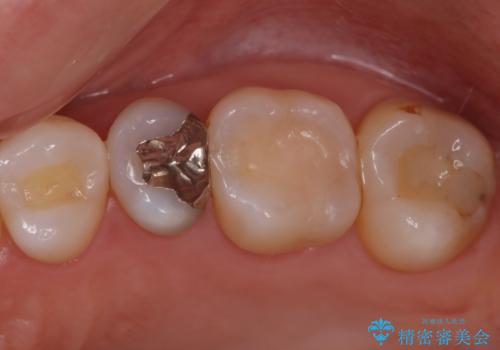

[ 歯肉縁下齲蝕 ] 歯周外科を行った虫歯治療